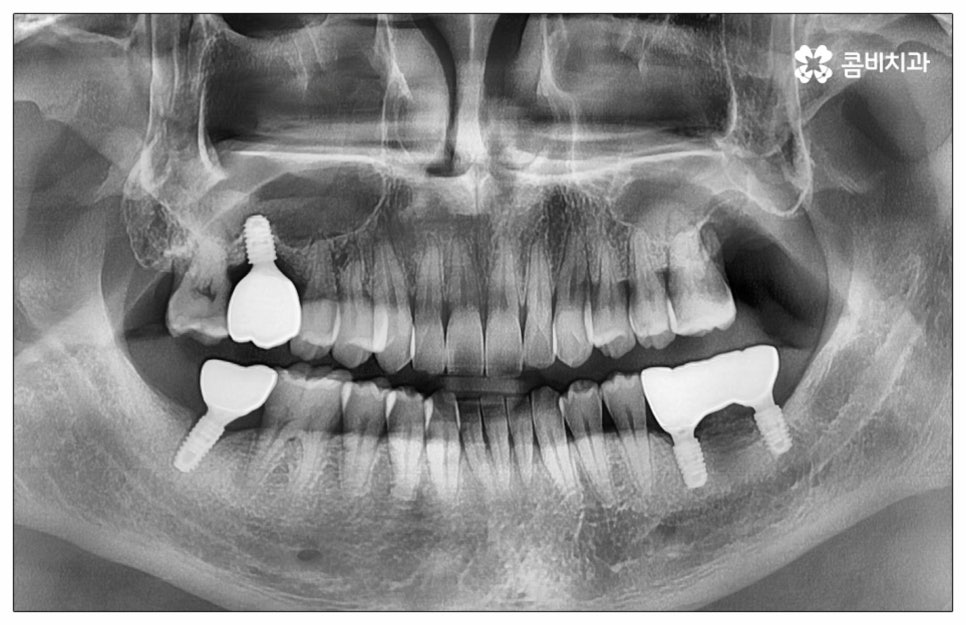

예전에는 이런 상황에서 틀니를 많이 이용하였으나 저작력 회복이 본래 자신의 치아 대비 20~30% 정도 밖에 되지 않고 잦은 탈락 위험 및 이물감, 잇몸을 눌러 장기적으로 잇몸뼈가 내려앉을 수 있다는 점 등 여러 가지 불편함이 있어 요즘은 임플란트 시술을 선호하시는 분들이 더 많아지고 있어요. 임플란트란 인체에 무해하며 잇몸뼈와 잘 결합하는 인공 치근을 잇몸뼈에 직접 식립하고 그 위로 기둥이 되는 중간 지대주와 치아 머리가 되는 크라운 보철물을 연결하여 인공 치아를 만들어 주는 시술을 말하는데, 자연 치아의 80% 정도 저작력 회복이 가능하기 때문에 식사를 할 때 음식을 크게 가리지 않아도 된다는 점 그리고 심미적으로 봤을 때 주변 치아와 자연스럽게 어우러진다는 점 때문에 각광을 받고 있습니다. 게다가 건강 보험 가입자이면서 만 65세 이상 부분 무치악 환자라면 평생 임플란트 2개까지 보험 적용을 받아 비용 부담을 줄일 수 있기 때문에 더욱 더 수요가 늘어나 이제는 치아 상실에 대체하는 대표적인 방법으로 임플란트 시술이 꼽히고 있는데요.

많이 대중화 되었다고 해도 임플란트 수술 자체가 술자의 숙련도에 크게 영향을 받는 복잡하고 고난도의 진료인 것은 틀림이 없기 때문에 담당 의료진이 해당 분야 임상 경험이 풍부한지, 뛰어난 기술력과 노하우를 가지고 있는지 꼼꼼하게 체크해 보실 필요가 있어요. 특히 노년층의 경우 당뇨, 고혈압 등 만성 질환을 앓고 있는 경우가 많아 혹시 상시 복용하고 있는 약이 있는지, 현재 환자 개개인의 상태는 어떤지, 사전 처치가 필요한 부분은 없는지 등등 수술 조건을 좀 더 까다롭게 평가한 후 환자분들과 이에 대해 충분히 상담하고 맞춤형 치료 계획을 세워 진행해야 하며 이를 위해 3D CT 와 같은 디지털 검진 장비를 통해 구강 내부 구조를 면밀하게 살피고 방대한 임상 데이터를 축적한 정품 임플란트 재료를 이용하여 연령이나 회복 정도를 살펴보면서 체력적 부담을 줄이는 방향으로 무리하지 않게 식립하는 것이 무엇보다 중요하다고 할 수 있습니다.

이때 추가 수술은 비급여 항목으로 건강보험임플란트 대상에서 제외되니 이에 대해서도 꼼꼼하게 살펴보시고 정밀 검진 후 담당 의료진과 자신의 상황에 대해서 충분하게 상담해 보시길 권유드리고 있습니다. 추가 수술의 대표적인 예로는 뼈이식 수술이 있는데요. 이것은 임플란트를 식립할 때 바탕이 되는 잇몸뼈의 높이나 폭, 밀도 등이 부족하다면 먼저 이를 보충해 주고 나서 임플란트를 심어주는 과정을 의미하며 같은 이유로 식립 성공률이나 장기적인 안정성을 높이기 위해 꼭 필요한 사전 처치, 즉 상악동 거상술 및 치주 질환 관련 수술 등을 먼저 해야 한다면 이 역시 추가 수술의 범주로 들어가니 자신의 상황에 대해서 상세하게 알아보실 필요가 있어요.